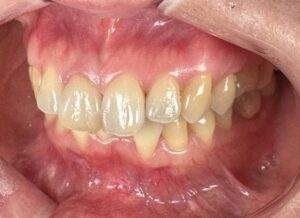

昨年 の 私 の 代表作 かも しれません。

全て セラミッククラウン修復 です。

歯周外科手術は 行なって います。